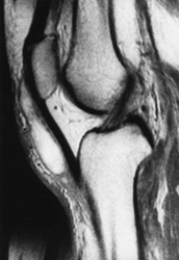

Which of the following imaging techniques illustrated in the pictures would be the most efficient to discover if there is a nerve root compression at the L4 level?

Q16: Which of the following imaging techniques illustrated

Q17: Which of the following imaging techniques illustrated